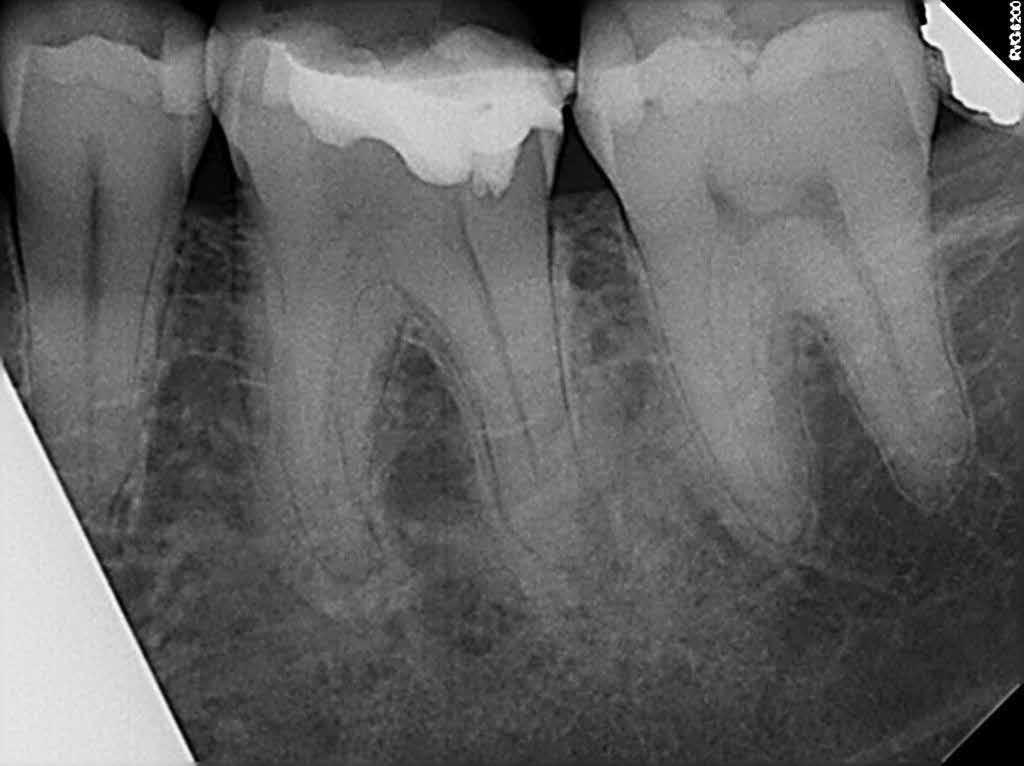

Anyagok és módszerek: 42 éves nő fordult a szerző rendelőjébe tüneti apikális parodontitisszel. A PA röntgenfelvételen az apex körül sugárzástól átlátszó kép és extrudált gyökércsatorna obturációs anyag volt látható, a CBCT-n megőrzött vestibuláris csont mellett (1–2. ábra). Mivel az elmúlt három évben kétszer

végeztek NSRCT-t, és a gyökércsatorna obturáció homogénnek, de túlságosan extrudáltnak tűnt, sebészi kezelés mellett döntöttek.

Szépen beállított ideiglenes korona volt jelen, kóros szondázási mélység és szondázási vérzés nélkül. Nem volt jelen sinus tractus (3–5. ábra). Tüneti apikális parodontitis 1. osztály (Von Arx&Cochrane 2001); B osztály (Kim&Kratchman 2005) és korábban elvégzett gyökérkezelés volt a végső diagnózis.